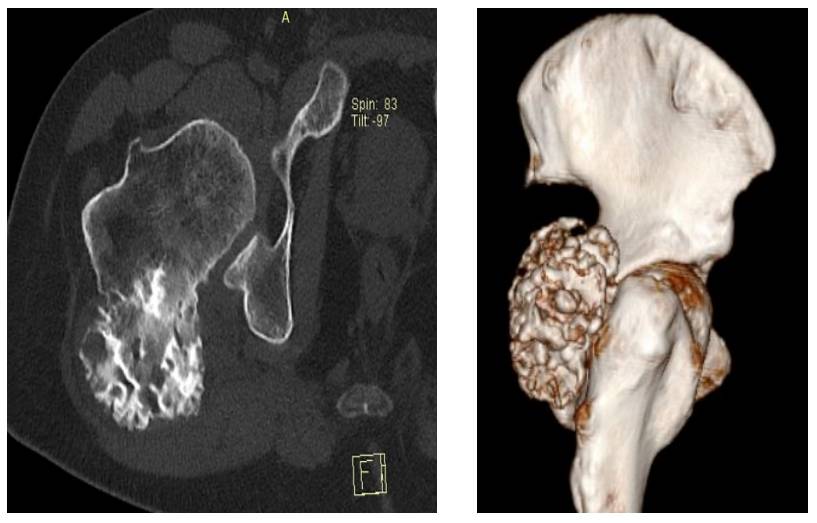

Before the surgery: The CT scan shows tumor tissue with irregular borders originating from the posterior proximal femur.